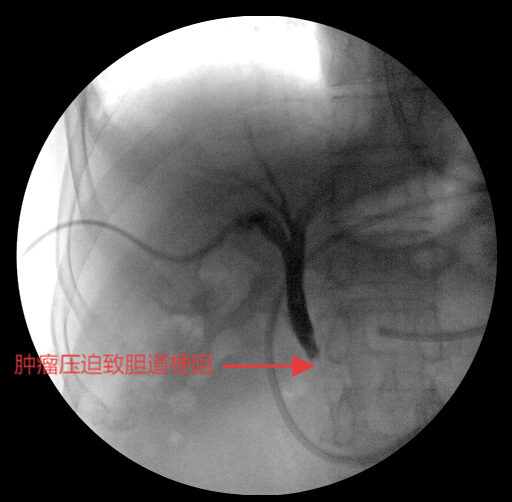

经皮肝穿刺胆道引流术(PTCD),术中造影提示胆道堵塞

手术在C型臂透视精准引导下开展:团队沿原PTCD通道送入“头发丝”细的导丝,首次穿刺即成功,精准选取最优胆道入路以规避组织损伤;导丝跨越梗阻段时,团队密切协作避免反复抽拉引发肠道逆行感染。针对外压性病灶导致的狭窄,先以球囊扩张狭窄部位,再将装载I-125的自膨式可载粒子胆道支架精准送入胆总管梗阻段并缓慢释放。术后造影显示,支架扩张效果良好,造影剂可通畅流入十二指肠,患者生命体征平稳。